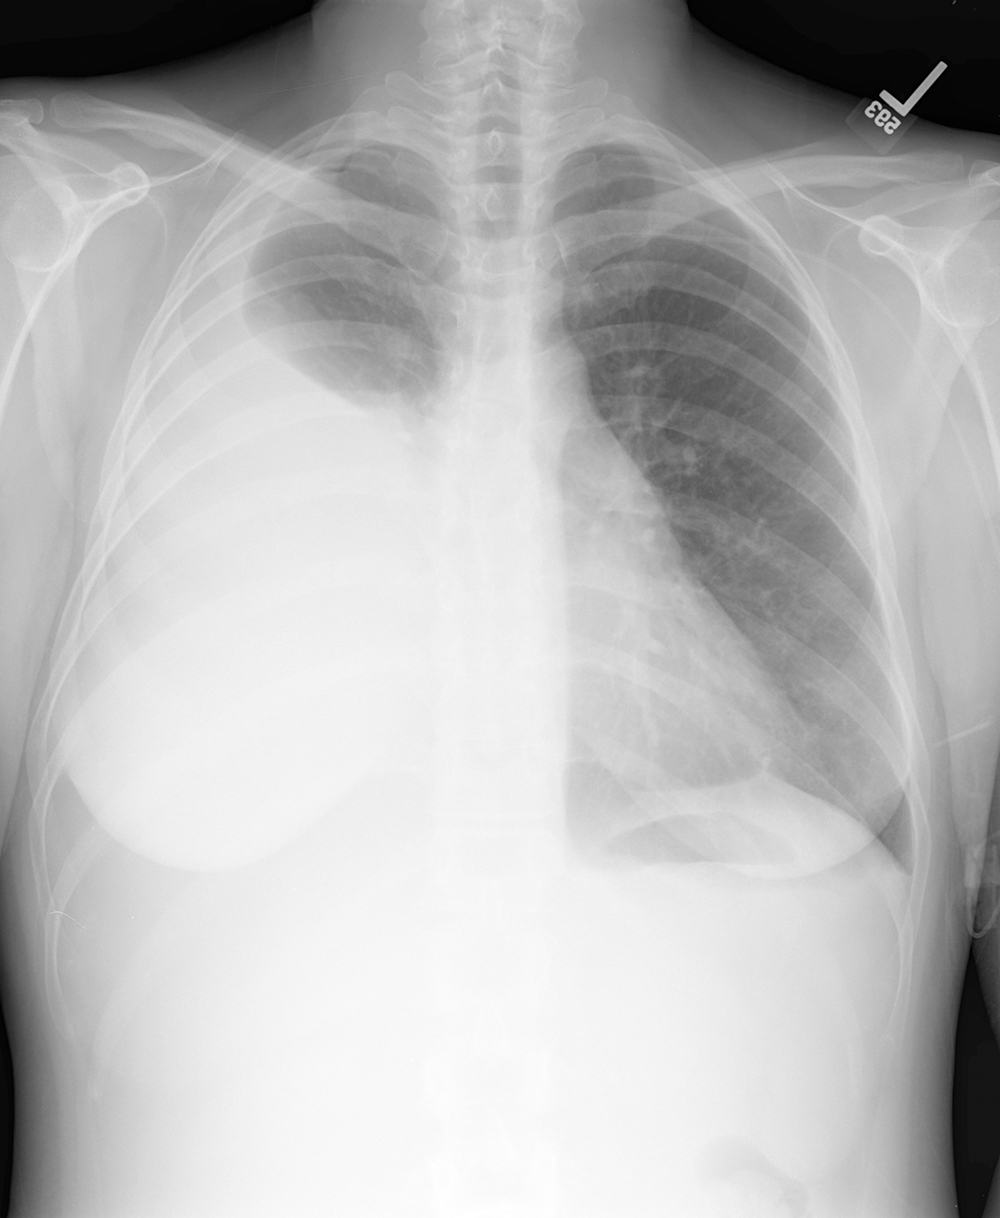

Topic 3

basic case for effusion

Further Explanation: